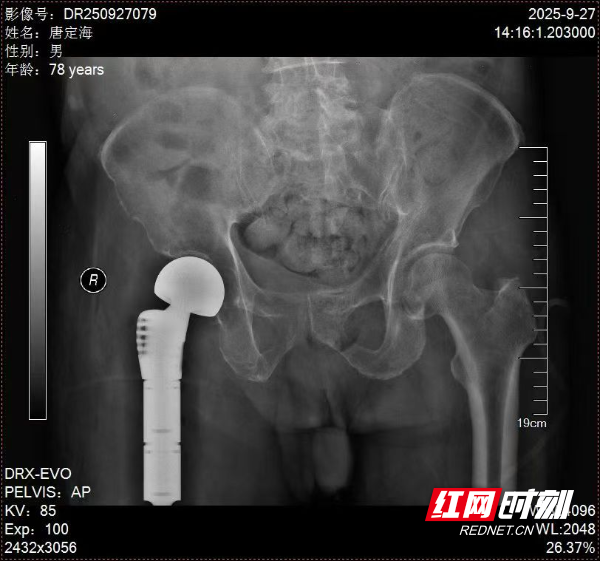

在征得家属同意后,手术由永州市中心医院首届知名专家、骨科一级顾问、主任医师叶明主刀。术中,他精准切除病变骨组织并植入人工髋关节,手术出血量远低于预期。